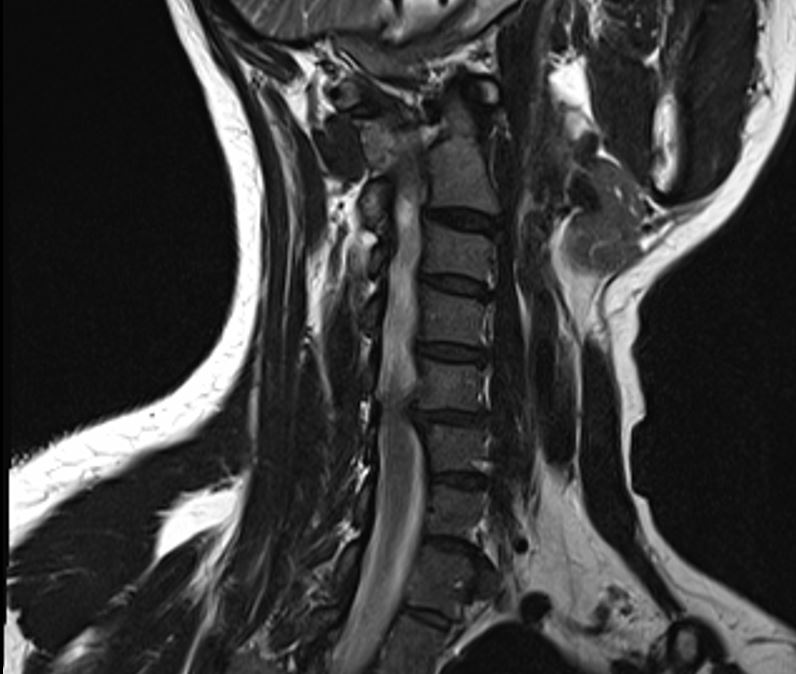

I also had a scan of my neck, and that did show something….one of my discs is a bit out of place…you can see it in the image below…fourth one from the top…

Not a major issue as yet…I don’t have any pain in my neck….and I was relieved that he said no surgery required.

But I do need to be careful not to damage it further…. no heavy weights for me…